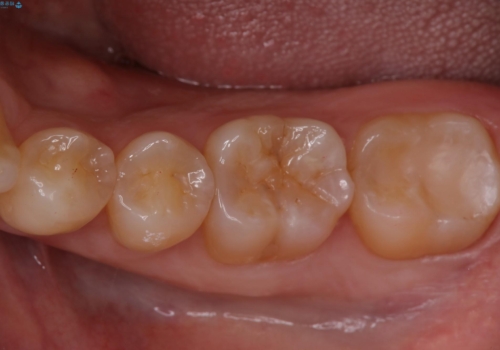

- 下の奥歯が黒いことが気になり来院された患者様です。

レントゲンなどから隣接面にも、う蝕があることが判明しました。

海外に引っ越す予定があり、見ため(審美性)強度ともに良い被せ物を希望されたため、セラミックインレーにて治療を行いました。